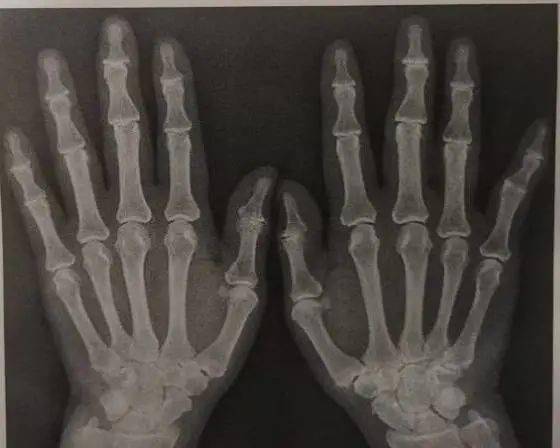

左手关节,手指关节

男,24岁,左手拇指指间关节外侧局部肿胀,质地较硬.手部外伤史.